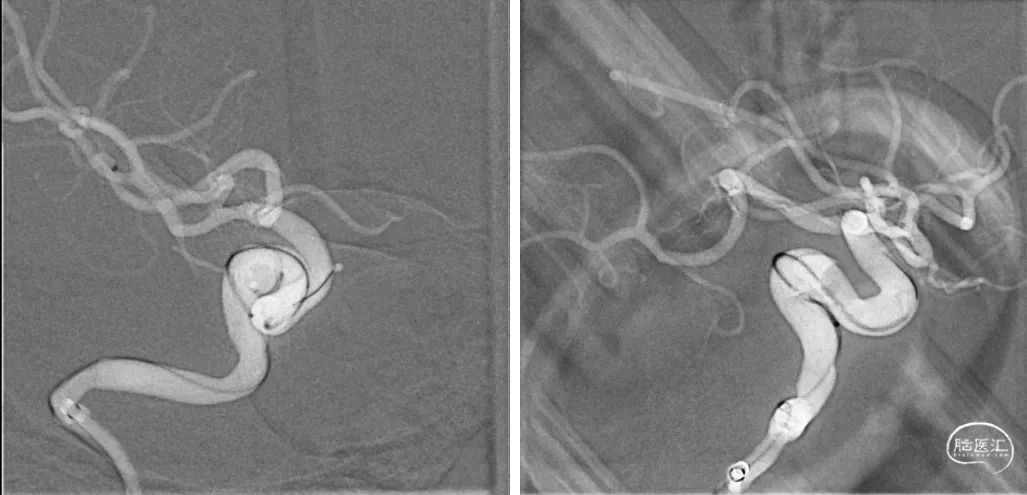

术前DSA影像检查:2024-01-10行脑动脉造影术,术中见右侧颈内海绵窦段动脉瘤,大小约6.9*5.5mm,瘤颈约4.6mm。

释放支架头端,远端锚定后,确认支架远端释放,贴壁良好,缓慢采用推挤方式将支架释放。

支架成功释放后,造影显示动脉瘤瘤颈支架覆盖贴壁良好,右侧颈内动脉通畅,右侧颈内动脉及分支血管显影良好,无血栓。